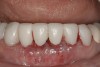

After the zirconia abutments were torqued to 20 Ncm, cotton and composite were used to cover the screw access openings. Figure 7 and Figure 8 show the finished feldspathic porcelain crowns on implants in sites Nos. 24 through 26, and on teeth Nos. 22, 23, 27, and 28; all crowns were cemented with dual-cure resin cement. Good remodeling of gingival architecture is also apparent in Figure 7. As predicted, the free gingival margin (FGM) on No. 23 is approximately 2 mm coronal to those of the adjacent implant crowns on Nos. 24 through 26 (Figure 7); as per the patient’s initial statement, this discrepancy was not an esthetic concern to her. Figure 9 shows the final post-restoration periapical view.

This patient faced a unique situation, perhaps not previously reported: retaining a healthy mandibular lateral incisor knowing this would create an esthetic compromise. Indeed, while the discrepancy in gingival-margin height is noticeable in retracted view (Figure 7), it does not show in full smile (Figure 8).

Figure 7  Finished feldspathic crowns, teeth Nos. 22, 23, 27, 28, and implant sites 24 through 26 showing good gingival emergence profile—post-cementation facial view.

Figure 7

Figure 8  Full smile—finished feldspathic crowns on teeth Nos. 22, 23, 27, and 28; implant crowns in sites 24 through 26; esthetic harmonization with opposing dentition.

Figure 8